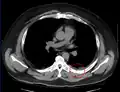

Fracture costale

La fracture costale, rupture d'une ou plusieurs côtes, rend la respiration douloureuse, difficile. Elle peut entraîner une atteinte des poumons, et notamment un hémothorax (le poumon se remplit de sang) ou un pneumothorax (le poumon a une « fuite d'air » et ne peut plus jouer son rôle), qui peut mettre en jeu le pronostic vital.